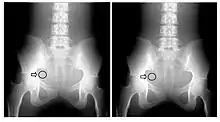

A second parameter to be derived from the transfer characteristic is the dynamic range, which expresses the range of input signals over which the image receptor is sensitive. In the case of CR, its about four orders of magnitude - see Figure 6.3, which shows its transfer characteristic in comparison to the traditional film/screen technology. The result is that under-exposure and over-exposure of regions traditionally seen radiographs are much less of an issue in clinical imaging. This feature of CR is illustrated by the radiographs in Figure 6.4.